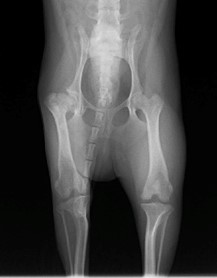

眼球摘出、眼瞼腫瘤切除、チェリーアイ整復、眼瞼縫合、瞬膜フラップ、眼球突出整復、耳介切除、垂直耳道切除、総耳道切除、鼻鏡切除、口腔腫瘍切除(上顎骨切除、下顎骨切除を含む)、各種抜歯(猫の全臼歯抜歯含む)舌腫瘍切除、唾液腺嚢胞切除、皮膚腫瘤切除、断脚(前肢、後肢、片側骨盤切除)、断尾、肺葉切除、胸腺腫切除、心膜切除、横隔膜ヘルニア整復、肝臓腫瘍切除、胆嚢摘出、胃切開、胃拡張胃捻転症候群整復、胃腫瘍切除、腸管切開、腸管腫瘍切除、直腸腫瘍切除(粘膜、全層プルスルーなど)、腎臓摘出、SUB設置手術、脾臓摘出、副腎摘出、膀胱切開、膀胱腫瘍切除(部分切除、全摘出、膀胱尿道一括切除など)、卵巣腫瘍切除、精巣腫瘍切除、卵巣子宮全摘出、肛門嚢切除、各種骨折、膝蓋骨脱臼整復、股関節脱臼整復、大腿骨頭切除、椎間板ヘルニア(各種椎弓切除術)、各種リンパ節切除 など